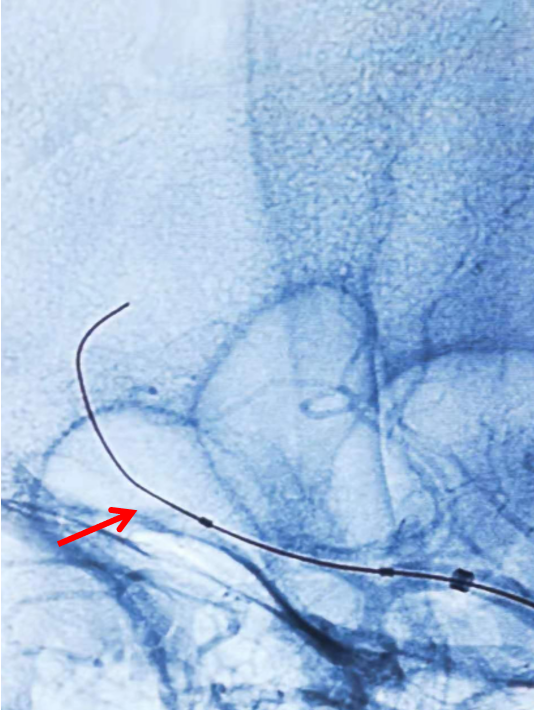

路途下,用5F的单弯造影管引导6F长鞘头端至右侧颈内动脉开口处,而后沿长鞘在泥鳅导丝的引导下将5F的115cm的Navien头端置于虹吸弯远端(下图箭头所示)。

再次造影证实右侧大脑中动脉上干、下干均闭塞(箭头示)。